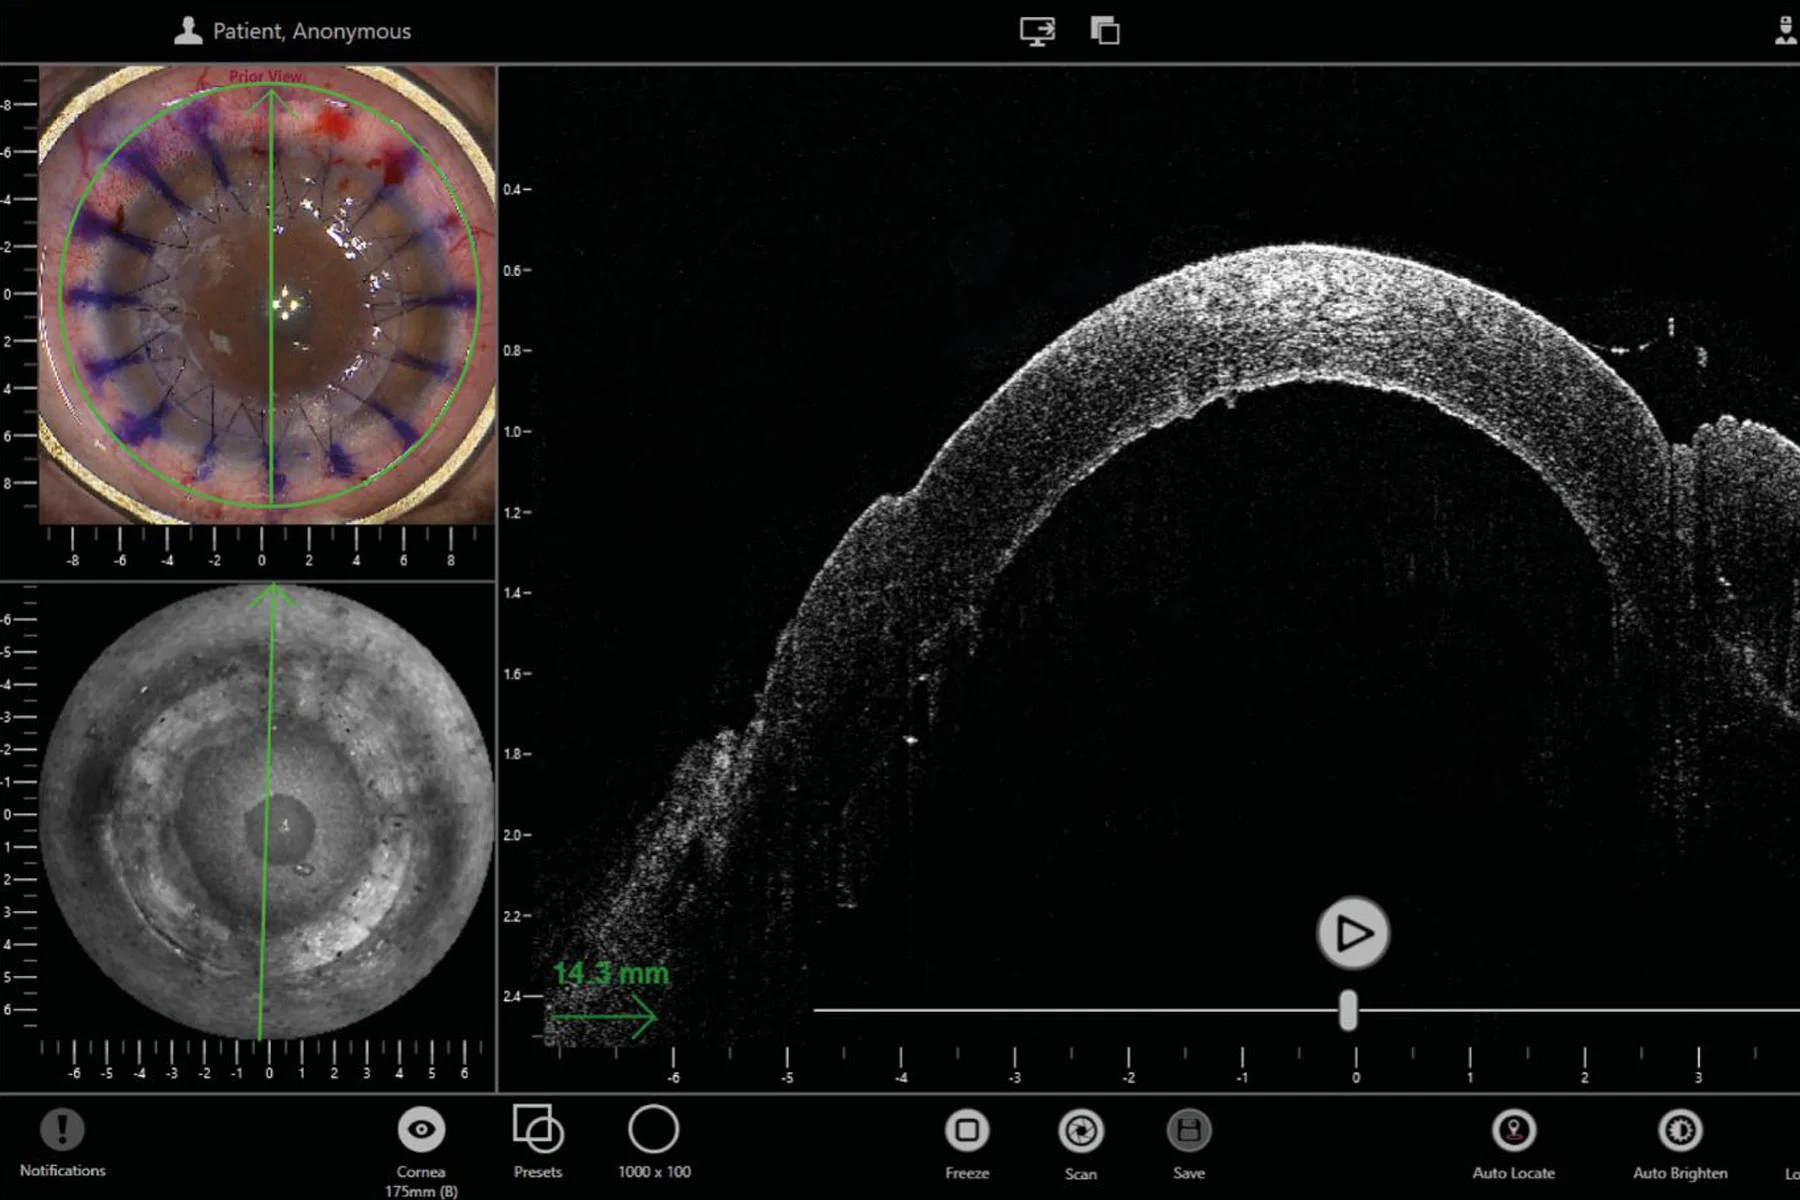

The EnFocus intraoperative OCT imaging system provides real-time confirmation of how ocular tissue is reacting to your surgical maneuvers. You can immediately adjust your surgical plan if needed for greater confidence in the surgical outcome.

Real-time display of 30 fps provides immediate feedback at each step e.g. to verify adherence of donor tissue in DMEK or DSAEK surgery

- Live on-screen measurements provide even more information e.g. cornea thickness and needle depth during DALK surgeries